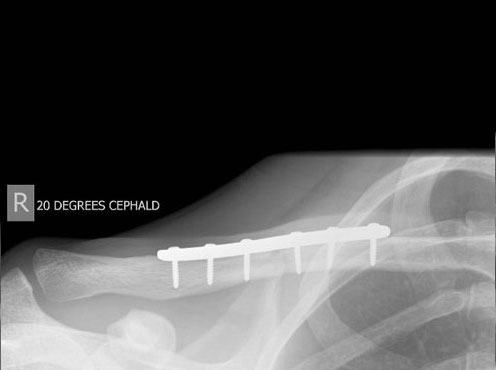

Generally all displaced fractures of the distal clavicle require surgery to increase the incidence of union. In my practice, the operation is performed by realigning the bones back to their original position using a plate and screws on top of the bone. The advantage of fixing them with a plate and screws generally means that you can start to move the arm a lot quicker and to also decrease the incidence of non-union.

How is the Operation Done?

The operation is performed with the patient under a general anaesthetic, in other words, completely asleep, and a small 3-4 cm incision is made under the collarbone, at the end of the shoulder. The fractured bone ends are exposed and put back into position using a plate and screws as shown below.

Click an image to enlarge